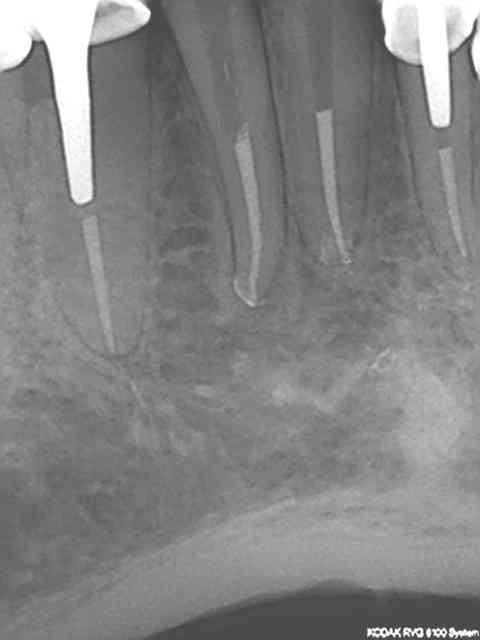

Regardez les endo de chicot29, mono cone et postez vos endo thermo et on compare !

Et effectivement un cone en 6 % n'a rien à voir avec un cone en 2%. L'efficacité tu la vois avec le temps, et un bon mono-cone scellé à l'apex donne des résultats plus que corrects. Je thermo-compacte au machtou quand je fais l'empreinte dans la séance de l'endo)))))

R1 c2o32p - Eugenol

R2 b6cnxj - Eugenol

R3 qrzatb - Eugenol

R4 dqlzan - Eugenol